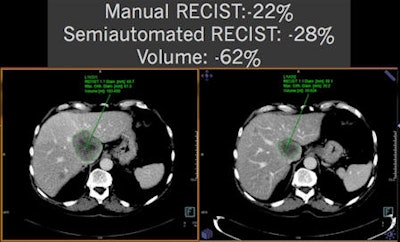

As shown in these cases, volumetry is more sensitive than RECIST measurements for determining therapy treatment response. All images courtesy of Dr. Anno Graser.

Semiautomated volumetry using a commercially available system and manual measurements of the longest RECIST 1.1 diameter and longest orthogonal diameter were performed. When comparing the manual measurements, the researchers found that simulating volume by extrapolating RECIST-based measurements would systematically overestimate tumor volume. However, volume simulations would be relatively accurate based on the World Health Organization (WHO) tumor burden criteria, Graser said.

In a recent multicenter evaluation of manual versus semiautomated measurements of tumor volume in lymphoma patients, researchers studied 59 patients with malignant lymphoma. The patients had 290 lymph nodes (5 ± 2 per patient) measured at baseline and follow-up (after two cycles of chemotherapy).

Manual measurements were performed at five German university hospitals for long axis diameter, short axis diameter, and WHO area. Semiautomated measurements of the same parameters and volume were also performed.